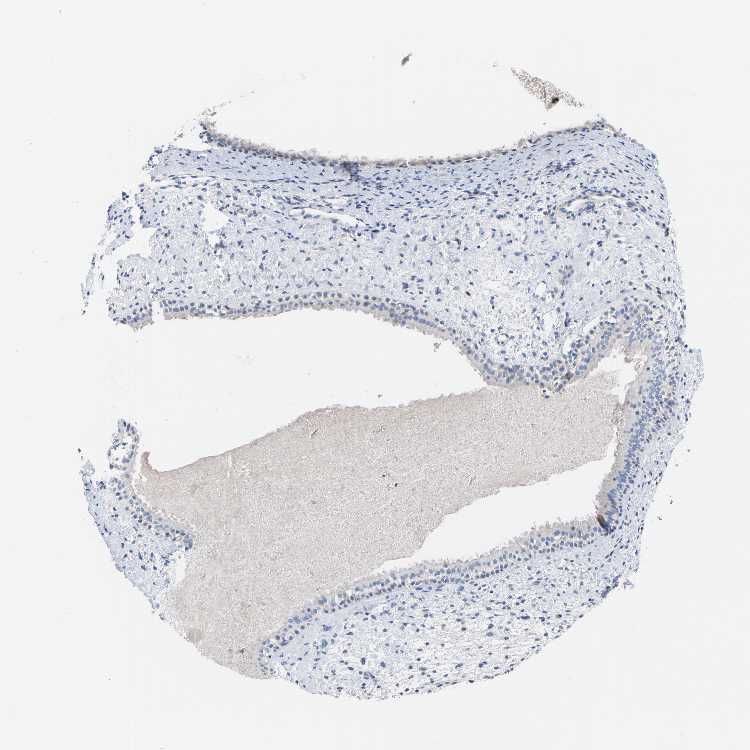

Nasopharynx